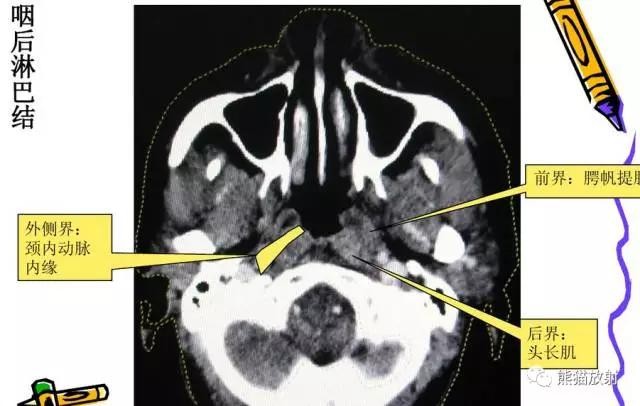

另:

女性,45岁,淋巴瘤。显示双侧腮腺区、左侧咽后区淋巴结增大,病变无融合倾向。